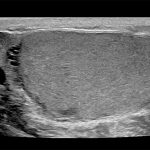

Imagini clinice:

Aplicatii: